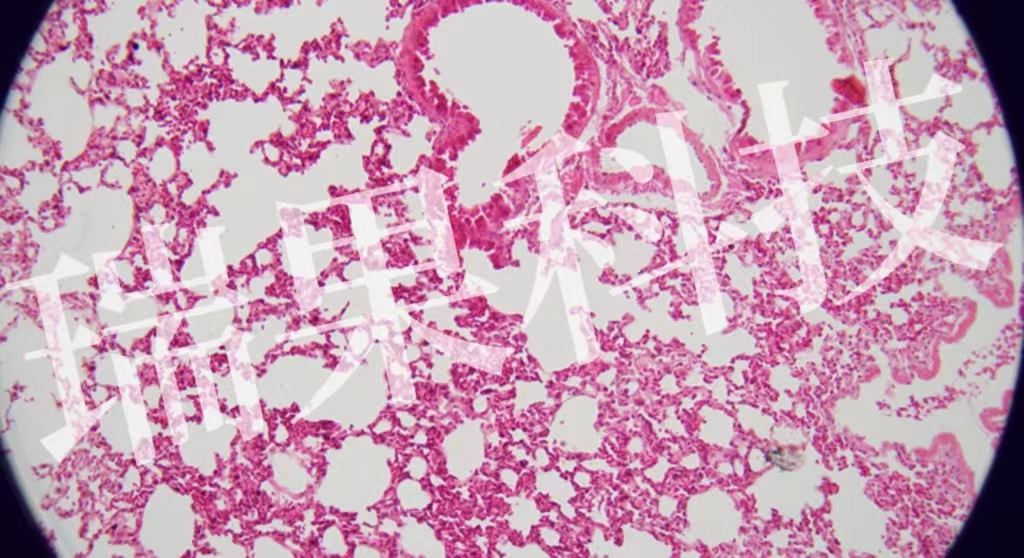

HE染色:蘇木精 - 伊紅染色法 ( hematoxylin-eosin staining ) ,簡(jiǎn)稱(chēng)HE染色法 ,石蠟切片技術(shù)里常用的染色法之一 。蘇木精染液為堿性 ,主要使細(xì)胞核內(nèi)的染色質(zhì)與胞質(zhì)內(nèi)的核酸著紫藍(lán)色 ;伊紅為酸性染料 ,主要使細(xì)

HE染色:蘇木精 - 伊紅染色法 ( hematoxylin-eosin staining ) ,簡(jiǎn)稱(chēng)HE染色法 ,石蠟切片技術(shù)里常用的染色法之一 。蘇木精染液為堿性 ,主要使細(xì)胞核內(nèi)的染色質(zhì)與胞質(zhì)內(nèi)的核酸著紫藍(lán)色 ;伊紅為酸性染料 ,主要使細(xì)胞質(zhì)和細(xì)胞外基質(zhì)中的成分著紅色 。HE染色法是組織學(xué)、胚胎學(xué)、病理學(xué)教學(xué)與科研中最基本、使用最廣泛的技術(shù)方法。